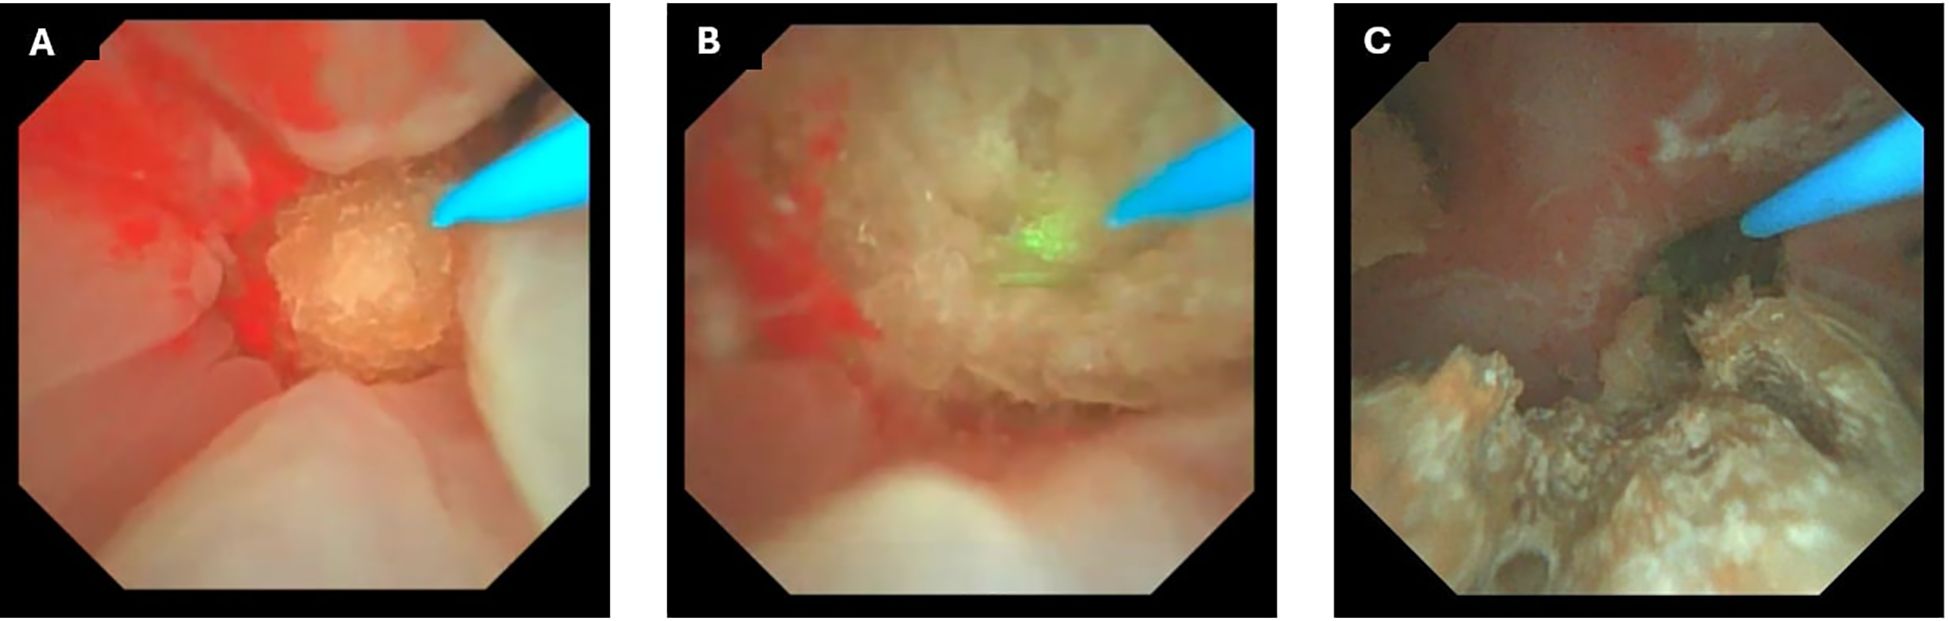

Intraoperatively (Figure 2), the incorporation of DISS and FANS provided significant advantages. The DISS system ensured a consistently clear surgical field, minimizing the need for irrigation and improving the accuracy of laser application. The FANS allowed for precise navigation of the renal calyces, enabling efficient fragmentation and retrieval of stone fragments (Figure 3). These advancements made the procedure remarkably straightforward, even for a large and complex staghorn stone. The surgery was completed within three hours, showcasing the efficiency and reliability of this technique. Quantitative intraoperative metrics are summarized in Table 1, including total operative time (170 minutes), laser activation time (95 minutes), irrigation fluid volume (11.5 L), and estimated blood loss (30 mL).

Figure 3. Intraoperative endoscopic views during retrograde intrarenal surgery (RIRS) with thulium fiber laser, Direct In-Scope Suction (DISS), and Flexible and Navigable Ureteral Access Sheath (FANS). (A) Initial visualization of a large staghorn stone before initiation of laser dusting and fragmentation. (B) Laser dusting in progress using thulium fiber laser, with visible ablation effect on the stone surface. (C) Intraoperative view following partial fragmentation, showing residual stone debris within the renal calyx.